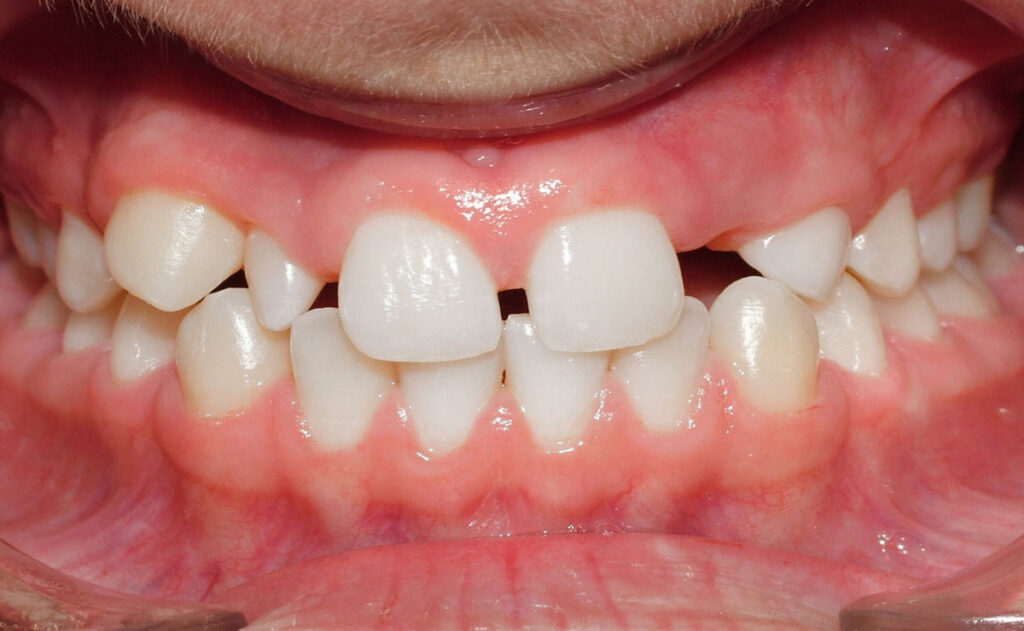

Le remodelage du sourire s’adresse à toutes les personnes souhaitant :